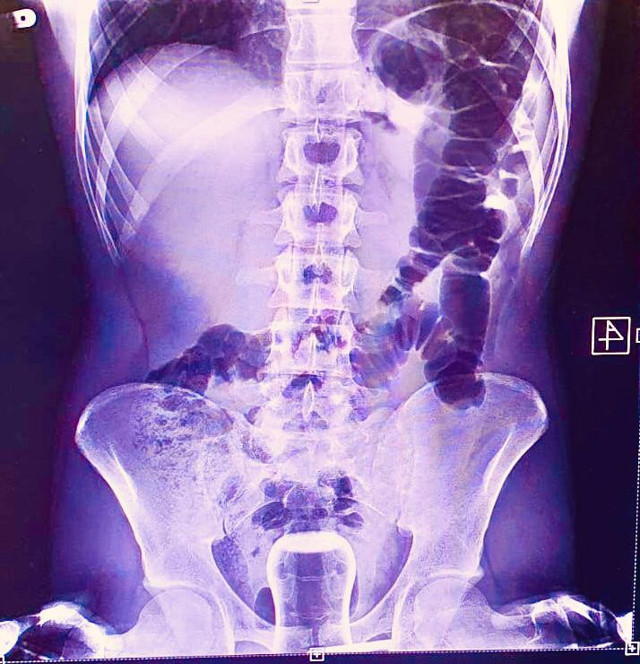

Abone olŞANLIURFA'da ismi açıklanmayan bir kişi Mehmet Akif İnan Eğitim ve Araştırma Hastanesine başvurdu. Acil serviste hastanın çekilen röntgeninde anüs bölgesinde çay bardağı görüldü. Çay bardağı, uzman doktorlar tarafından gerçekleştirilen operasyonla çıkarıldı.

Ameliyatla sancıdan kurtulup eski sağlığına kavuşan hasta, doktorlara uzun zamandır basur hastası olduğunu, hacamatçıya gittiğini ve yağlı çay bardağın kazayla anüs bölgesine kaçtığını ileri sürerek ameliyattan dolayı teşekkür etti.